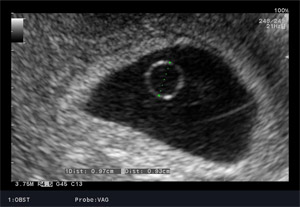

We wczesnej ciąży najlepszy obraz daje sonda dopochwowa. Badanie musi odpowiedzieć nam na pytanie czy ciąża jest pojedyncza, czy mnoga? Czy jest żywa? Czy jest prawidłowo umiejscowiona? Z tego względu badanie USG przewyższa znacznie testy ciążowe. Od 4 miesiąca stosowane są przede wszystkim sondy przez brzuszne. Aktualnie Polskie Towarzystwo Ginekologiczne zaleca wykonanie w ciąży prawidłowej trzech badań USG: około 11 – 13+6 tygodnia ciąży, około 18 - 24 tygodnia ciąży oraz 28 - 32 tygodnia ciąży. Każde z tych badań ma celu ocenę aktualnego rozwoju i dobrostanu płodu. W niektórych przypadkach możliwe jest przewidywanie zagrożenia ciąży na kilka tygodni wcześniej.

USG prenatalne 11 - 13+6 tydzień ciąży

Jest to badaniem przesiewowym wykonywanym między 11 a 13+6 tygodniem (13 tygodni i 6 dni), które ma ułatwić wykrycie zespołu Down’a (trisomii 21 pary chromosomów) i trisomii 18 pary chromosomów. Badanie ultrasonograficzne wraz z badaniami biochemicznymi (białko: PAPP-A oraz wolną podjednostką beta hCG) określa ryzyko wystąpienia wad rozwojowych płodu, pozwala na ocenę rozwoju płodu. W pewnych przypadkach zalecane są dalsze, bardziej szczegółowe badania – oznaczanie DNA płodowego lub amniopunkcję genetyczną i prenatalne badanie ultrasonograficzne między 18-24 tygodniem ciąży.